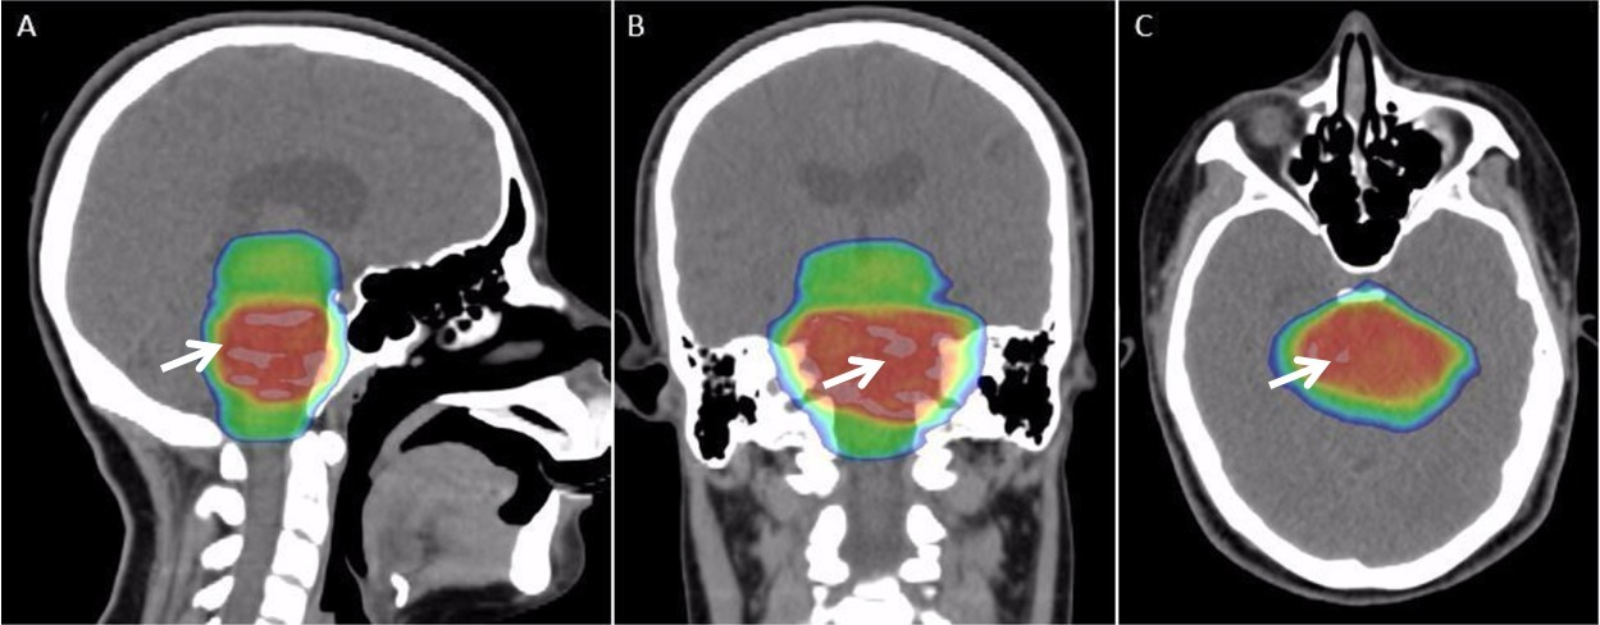

현대 방사선 치료는 CT 스캔을 사용하여 종양과 주변 정상 구조를 식별하고 복잡한 방사선 치료 계획을 수립하기 위한 선량 계산을 수행한다. 환자는 치료 영역의 위치를 안내하기 위해 피부에 작은 표시를 받는다.[10] 환자의 자세는 매우 중요하며, 마스크와 쿠션 등 환자의 신체에 맞출 수 있는 다양한 환자 고정 장치가 개발되었다.

현대 방사선 치료는 CT 스캔을 이용하여 종양과 주변 정상 구조를 식별하고, 복잡한 방사선 치료 계획을 수립한다.[10] 환자는 치료 영역의 위치를 안내하기 위해 피부에 작은 표시를 받으며,[10] 치료 시 동일한 자세를 유지하는 것이 중요하기 때문에 환자 고정 장치가 사용된다. 영상 유도 방사선 치료는 영상을 통해 치료 위치 오차를 수정하는 방법이다.

컴퓨터 단층 촬영(CT) 영상을 기반으로 종양의 3차원적인 형태를 파악하여 방사선을 조사하는 방법이다. 3차원 입체 조형 방사선 치료(3DCRT)에서는 빔의 눈 관점에서 다엽 콜리메이터(MLC)와 가변적인 수의 빔을 사용하여 각 방사선 빔의 프로파일을 종양의 프로파일에 맞춘다. 치료 부위가 종양의 형태에 맞춰지면 주변 정상 조직에 대한 방사선의 상대적 독성이 감소하여 기존 기술보다 종양에 더 높은 선량의 방사선을 전달할 수 있다.[10]3. 1. 3. 세기 변조 방사선 치료 (Intensity-Modulated Radiation Therapy, IMRT)

컴퓨터로 제어되는 X선 가속기는 악성 종양이나 종양 내 특정 부위에 정확한 방사선량을 분배한다. 방사선 조사 패턴은 최적화 및 치료 시뮬레이션(치료 계획)을 수행하기 위해 맞춤형 컴퓨팅 응용 프로그램을 사용하여 결정된다. 방사선 빔의 세기를 제어하거나 변조하여 방사선량이 종양의 3차원 형태와 일치하도록 한다. 종양의 대부분을 차지하는 부위(gross tumor volume) 근처에서는 방사선량 강도를 높이고, 인접한 정상 조직의 방사선량은 감소시키거나 완전히 피한다. 이는 3DCRT보다 더 나은 종양 표적화, 감소된 부작용, 향상된 치료 결과를 가져온다.